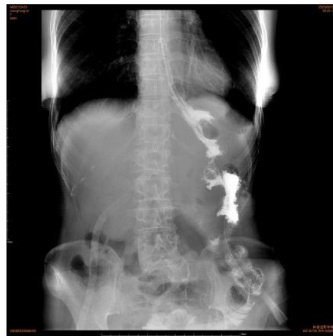

关键词:胃癌;胃肠间质瘤;空肠;瘤样钙盐沉积症

胃肠间质瘤(Gastrointestinal stromal tumors,GIST)是罕见疾病,合并胃癌的病例尤为罕见,而瘤样钙盐沉积症发生在空肠的病例尚无国内文献报道。(剩余3752字)

胃癌合并胃间质瘤和空肠瘤样钙盐沉积症1例